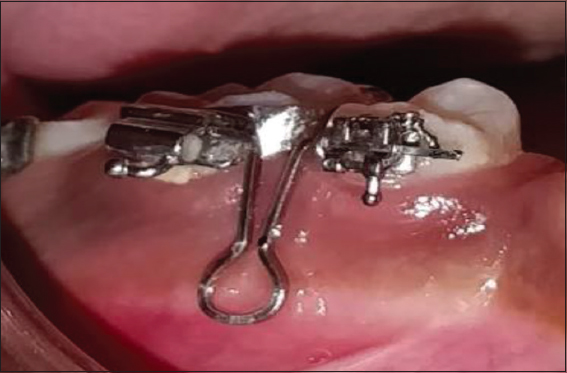

Resonance frequency analysis was used to gauge the implant’s stability. The principle for RFA assessment is the detection of the mini magnet embedded in the aluminum housing of an implant head, known as a smart peg [Figure 6]. The main unit of assessment is the resonance frequency emitted by the magnet. Because no Smart Pegs available are suitable for the orthodontic mini-implants a customized connector will be used for attachment between the two. The readings were recorded(T0) after insertion, (T1) 24 hours after insertion, (T2) 2 weeks after insertion, (T3) 4 weeks after insertion, (T4) 6 weeks after insertion, (T5) 8 weeks after insertion. Mean values were calculated for all six (3 in mesiodistal and 3 in occlusogingival directions) readings and that will be the overall ISQ value for each micro implant at each time [Figures 7-9]. The higher the ISQ values the greater will be the stability and hence the optimal loading time.

thumb

Figure 6: Smart Peg and customized connector engaged with the micro-implant head